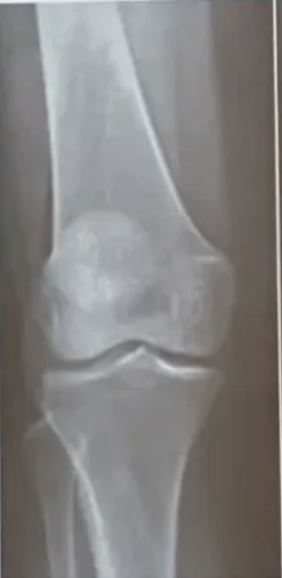

Rx se puede observar

A

• Engrosamiento y esclerosis de la lámina subcondral

• Osteofitos en borde articular

• Distensión de cápsula articular

• Cambios en tejido blando periarticular

Rodillas

• Deformidad → genu varo

• Quistes subcondrales

• Erosiones centrales

• Meseta tibial

osteofitos

Clasificación rx artrosis donde hay ausencia de osteofitos, estrechamiento o quistes

Clasificación rx artrosis donde solo hay osteófitos y dudoso pinzamiento de espacio articular

Grado 1 = dudoso

Clasificación rx artrosis donde hay osteófitos pequeños que estrechan la interlínea moderada, +/- quistes y esclerosis. Claro pinzamiento

Grado 2 = Mínima

Q

Clasificación rx artrosis donde hay osteófitos grandes, estrechamiento de interlinee muy evidente. Colapso de espacio articular, esclerósis severa y deformidad ósea

Grado 4 = Severa